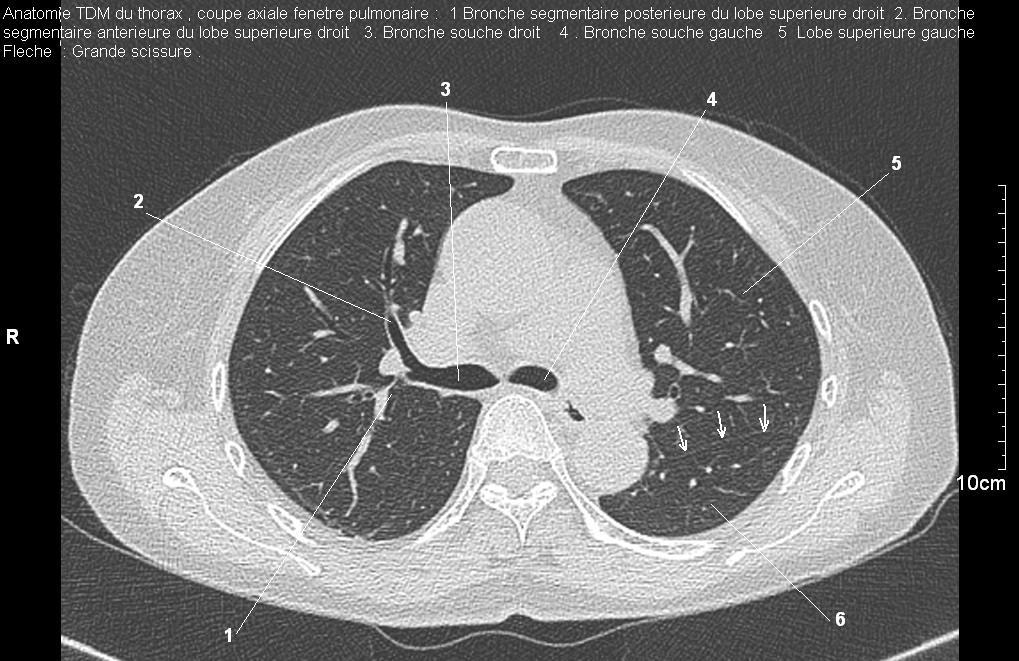

Radioanatomie pulmonaire ( image radiologie thoracique normale )- La Tomodensitometrie du  thorax ( coupes axiales fenetre pulmonaire )

Les fenetres parenchymateuses permettre d'etudier anatomie du poumon et juger sur les lesions du parenchyme pulmonaire en coupes axiales de 0,5-1cm sur le thorax .